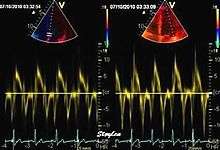

Tissue Doppler echocardiography (Also called Tissue Doppler Imaging - TDI or Tissue Velocity Imaging - TVI) is a Medical ultrasound technology mainly used in Echocardiography that measures the velocity of the heart muscle or myocardium through the phases of one or more heartbeats by the Doppler effect (frequency shift) of the reflected ultrasound. The technique is the same as for Doppler echocardiography, measuring flow velocities. Tissue signals however, have higher amplitude and lower velocities, and the signals are extracted by using different filter and gain settings. Like Doppler flow, Tissue Doppler can be acquired both by spectral analysis (Spectral density estimation) as pulsed Doppler [1] and by the Autocorrelation technique as colour Tissue Doppler [2] (Duplex ultrasonography). While pulsed Doppler only acquires the velocity at one point at a time, colour Doppler can acquire simultaneous pixel velocity values across the whole imaging field. Pulsed Doppler on the other hand, is more robust against noise, as peak values are measured on top of the spectrum, and are unaffected of the presence of clutter (stationary reverberation noise).

This has become a major echocardiographic tool for assessment of both systolic and diastolic ventricular function. However, as this is a spectral technique, it is important to realise that measurement of peak values is dependent on the width of the spectrum, which again is a function of gain setting.

Pulsed wave spectral Tissue Doppler has become a universal tool that is part of the general echocardiographic examination. Like any other echocardiographic measurement, measures by tissue Doppler should be interpreted in the context of the whole examination. The velocity curves are in general taken from the base of the mitral annulus at the insertion of the mitral leaflets, in the septal and lateral points of the four chamber view, and eventually the anterior and inferior points of the two-chamber views. For the right ventricle it is customary to use the lateral point of the tricuspid annulus only.Averaging peak velocities from the septal and lateral point has become common, although it has been shown that averaging all four points mentioned above, gives significantly less variability[3]

The method measures annular velocities to and from the probe during the heart cycle.

Annular velocities summarises the longitudinal contraction of the ventricle during systole, and elongation during diastole. Peak velocities are commonly used.